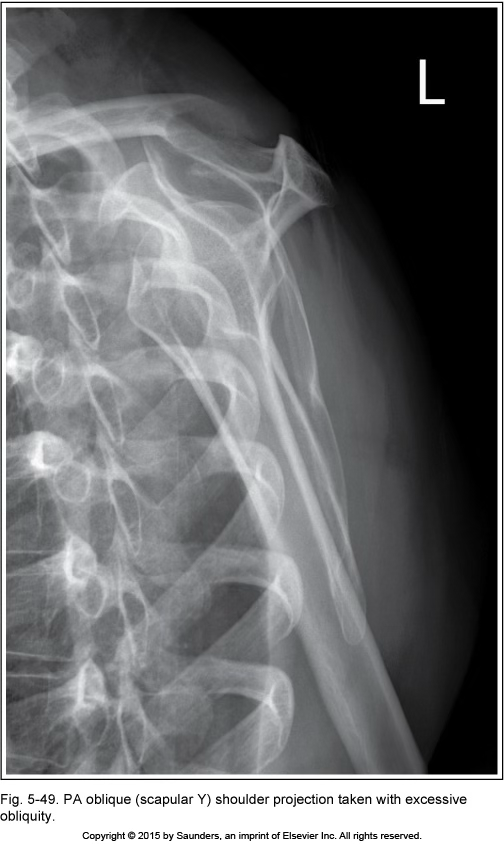

Y view

excessive obliquity